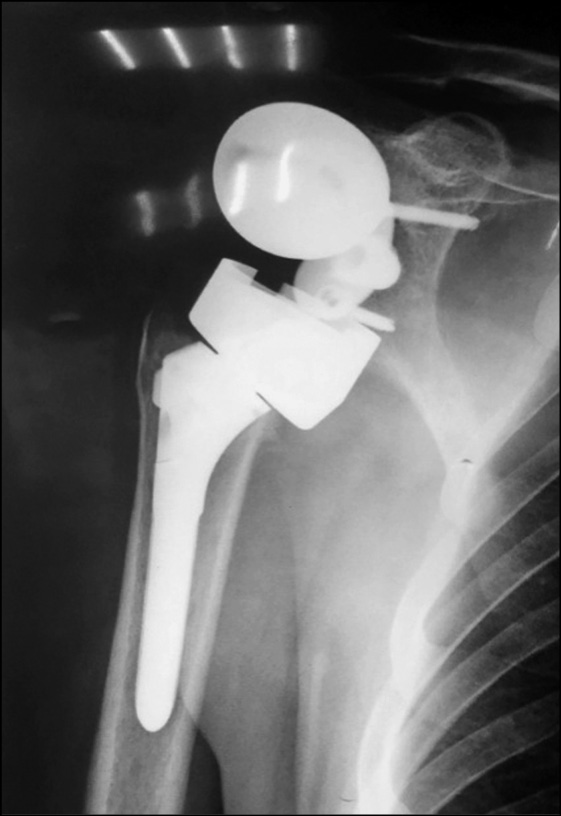

При клиническом и рентгенологическом обследовании пациентов выявлено 2 случая (8,7 %) перипротезного перелома, 1 из которых произошел интраоперационно. У 3 пациентов (13,2 %) выявлен вывих эндопротеза: зафиксировано 2 случая вывиха плечевого компонента, вследствие ранних сроков нагрузок и объемов движений прооперированной конечности (рис. 1), а 1 пациент пострадал от разобщения гленосферы с метагленом, и в последствие ее вывихом (рис. 2).

Рис. 1. Рентгенограммы пациентов с вывихом плечевого компонента реверсивного эндопротеза плечевого сустава

Fig. 1. Patients’ X-ray with shoulder component dislocation of a reverse shoulder joint endoprosthesis